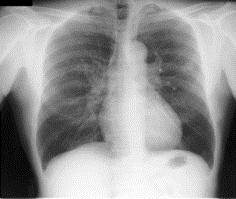

Figure 1: Shenzhen data set sample. (a) X-Ray (b) Mask.

Two data sets were used for this experiment. We used the Montgomery data set and the Shenzhen data set. The National Institute of Health and the National Library of Medicine maintain these data sets. In the Montgomery data set, there is a total of 138 images with a size of 4020 * 4892. 58 abnormal images show signs of a wide range of diseases and there are 80 normal cases. Shenzhen X-Ray data set is made up of 662 frontal chest X-Ray with 326 normal cases and 336 abnormal cases. The samples are in PNG format. Images are roughly 3000*3000 in size. Figure 1 and Figure 2 show sample from our data set.